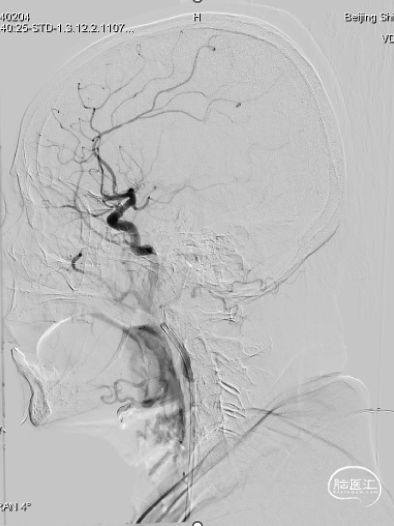

➤通过狭窄处造影

将8F导引导管+璞慧 5F 125cm WellThru™支撑导管组合后选入右颈内动脉C4段,将微导管连同0.014" 微导丝沿支撑导管小心通过闭塞处,微导管头端置于右大脑中动脉M1段分叉处上干,由微导管造影显示:右大脑中动脉M1段为血栓征象。

➤第一次取栓后造影

将4×20mm 支架预装入微导管,打开支架约5分钟,璞慧 5F 125cm WellThru™支撑导管置于M1段顶住血栓,于右大脑中动脉M1段血栓处拉栓并抽吸1次,取出支架,内见2个血栓,造影示M1段远端显影,血流1级。

➤术后造影

后又经过两次取栓后,观察10分钟造影显示:造影右大脑中动脉显影好,远端血流可,未再闭塞,手术结束。

➤栓子

➤术后影像

手术时间点

发病时间:2024.04.08 22:00

就诊时间:2024.04.09 11:27

穿刺时间:2024.04.09 15:40

再通时间:2024.04.09 16:48

发病至穿刺:17h40min

就诊至穿刺:2h13min

发病至再通:18h48min

就诊至再通:3h21min

术后情况

![]()

出院时情况:神志清楚,可简单对答。双侧瞳孔等大圆,直径2.5mm,对光反射灵敏。眼动充分,眼震阴性。左侧鼻唇沟浅,左侧示齿无力。伸舌左偏,左上肢肌力近端2级,远端3级,左下肢4-级,右侧上下肢肌力5-级。左侧腱反射较右侧活跃。左下肢Babinski、Chaddock征(+)。

(1)患者突发起病,93岁高龄,发病时间到本院就诊时间间隔近14个小时,晨起发现患者左侧肢体力弱,完全不能活动,伴双眼向右侧凝视,伴嗜睡、言语不清。头CTA显示右侧大脑中动脉M2段以远闭塞,远端少许侧支循环形成。

(2)病人血管迂曲,璞慧 WellThru™支撑导管裸奔顺利到位,通过采用中间导管+取栓支架进行远端血栓捕捉,三次取通闭塞血管。